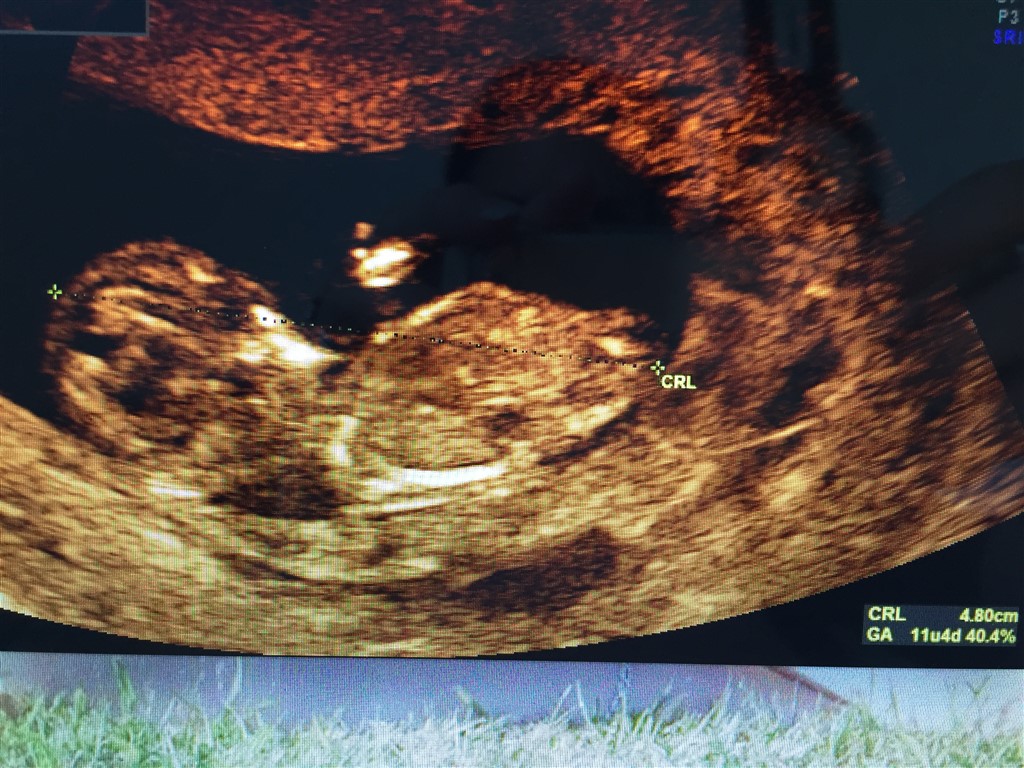

Du skal hellere sætte almindelig scannings billede ind. Så det "nemmere" at se end i 3D

Vi har ikke været til nf skanning endnu så det var egentlig bare for sjov fordi vi selv var lidt uenige. Men kan da lige sætte et billede ind her

Vedhæftede fotos (klik for at se i fuld størrelse)